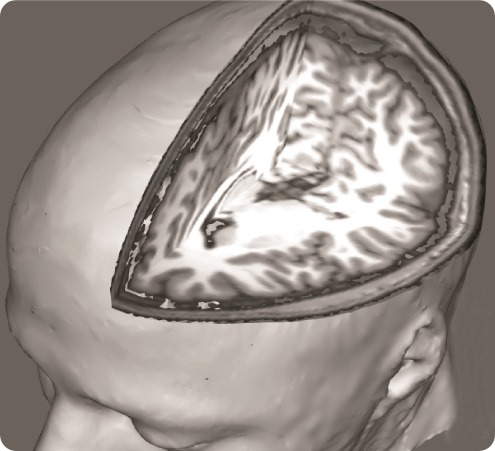

Fibro brain 1 - resized

In order to address this question, we used a brain imaging technique called ‘functional Magnetic Resonance Imaging’, which allows us to examine how brain activity changes in association with certain states or tasks.